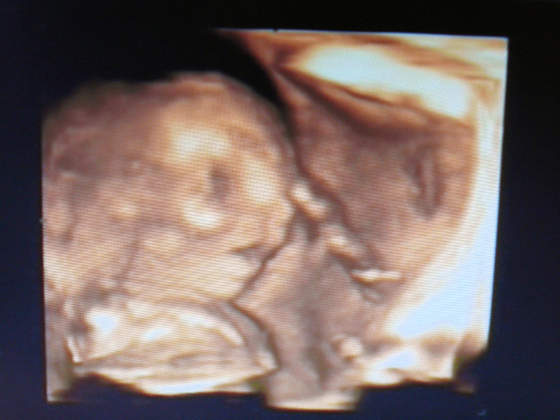

a oto mój synek w połowie drogi :-) (22 tydzień)

może trochę nie wyraźne - ale ja tam widze podobieństwo do męża hihihi